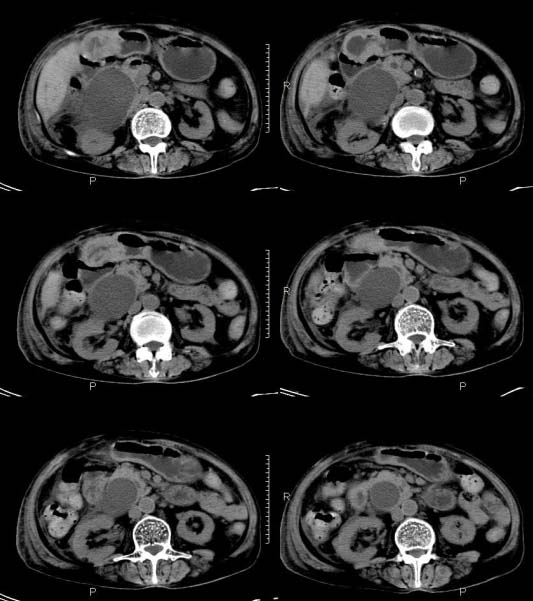

女,71岁,腹痛、腹胀、黄疸20余天,b超示肝内外胆管高度扩张内伴絮状物质(未提示梗阻部位或结石影),经抗炎解痉治疗后,肝功能有所好转,但胆道梗阻状态并未减轻。患者曾于1970年代做过胆囊切除术,1997年因胰腺炎而手术;且患者有糖尿病10余年。ct图片传了静脉期,未传动脉期了,最后一序列为3.2mm薄扫,请各位同仁仔细看看,确定一下胆管梗阻的部位,是炎性梗阻还是肿瘤性梗阻,是否与胰腺炎有关系,扩张胆总管中段前缘是否是胰管。请高手们最好用图示来指出梗阻部位。

请大家看看扩张的胆总管内见一弧线形间隔,怎样解释?

肝内外胆管显著扩张,考虑先天性胆管囊肿(ⅳ型)。

肝内胆管远侧、近侧不比例扩张,以近侧为明显。胆总管扩张。考虑先天性胆管囊肿(ⅳ型)。